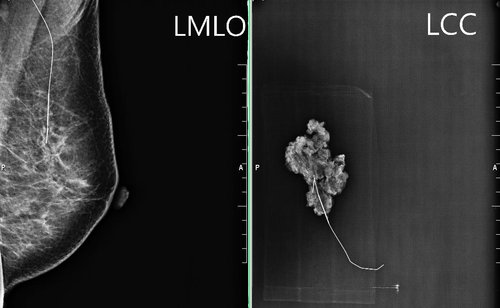

零期乳癌----乳房原位癌的臨床表現、診斷與治療 (1):乳腺管原位癌(ductal carcinoma in situ, DCIS)